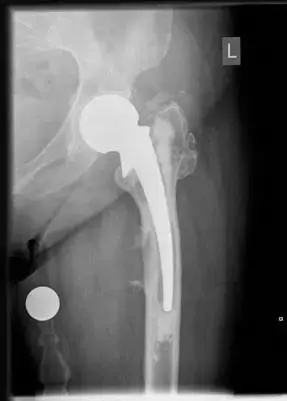

صورة توضيحية لـ آلام مفصل الفخذ: الأسباب، الأعراض والعلاج في صنعاء | د. محمد هطيف

2. استبدال مفصل الفخذ الكلي (Total Hip Arthroplasty - THA):

• متى يُستخدم؟ هو الحل الأمثل لحالات خشونة المفصل المتقدمة، النخر اللاوعائي الشديد، أو الكسور المعقدة التي لا يمكن إصلاحها.

• التقنية: يتم استبدال رأس الفخذ التالف والحُق بمفصل اصطناعي يتكون من مكونات معدنية وبلاستيكية أو سيراميكية.

• المزايا: تخفيف جذري للألم، استعادة كبيرة لنطاق الحركة والقدرة على المشي والقيام بالأنشطة اليومية.

• خبرة الدكتور هطيف: يتمتع الأستاذ الدكتور محمد هطيف بخبرة تزيد عن 20 عاماً في إجراء جراحات استبدال مفصل الفخذ، ويستخدم أحدث أنواع المفاصل الصناعية وأكثرها متانة، بالإضافة إلى تقنيات جراحية متقدمة لتقليل المضاعفات وتحسين النتائج طويلة الأمد. يشتهر بدقته الجراحية التي تضمن أفضل استقرار ووظيفة للمفصل الجديد.